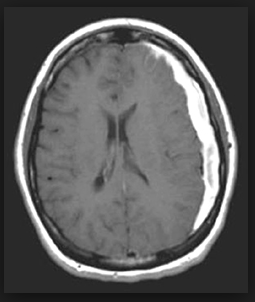

COMO SE CLASSIFICA O TEC DE ACORDO COM A GRAVIDADE?

TEC LEVE (GLASGOW 13-15)

TEC MODERADO (GLASGOW 9-12)

TEC GRAVE (GLASGOW 3-8)